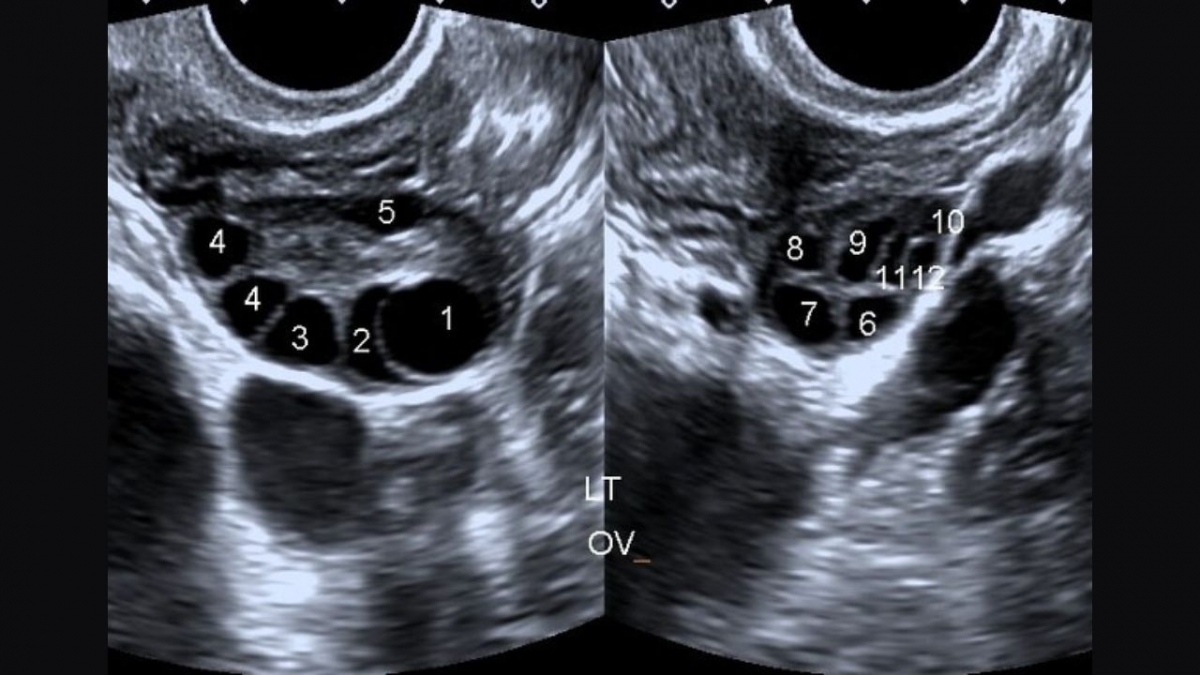

- Siêu âm thấy hình ảnh buồng trứng có nhiều nang nhỏ